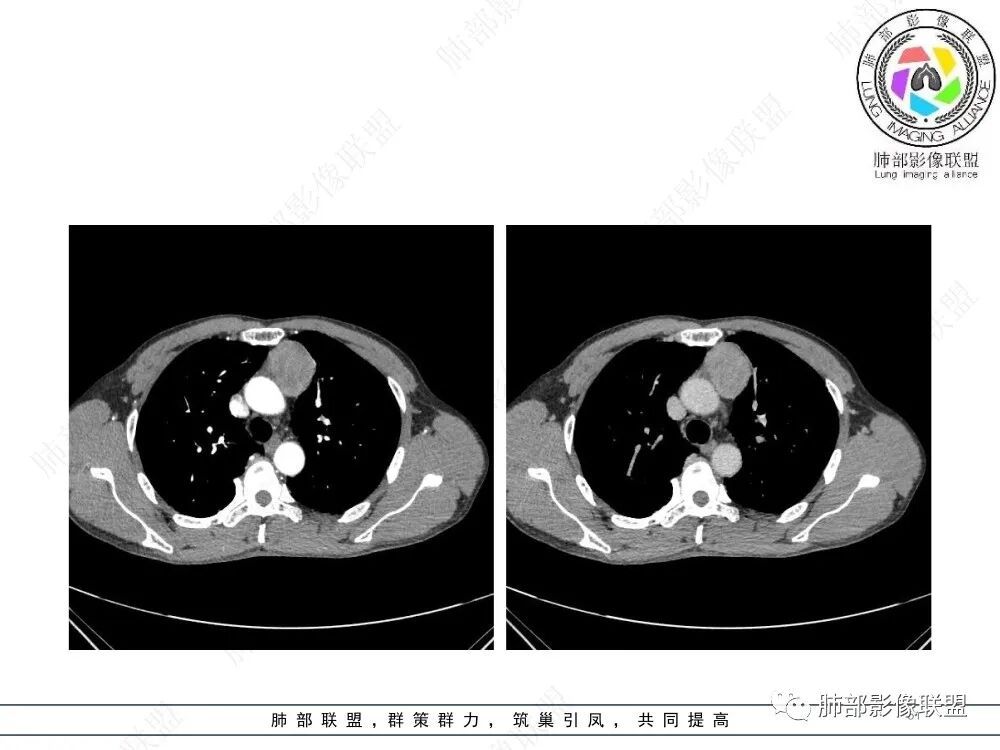

放射小白:男性47岁,前纵隔团块状占位,边界尚清,增强中度强化,内部疑似纤维分隔,常规考虑胸腺瘤可能(A/AB型),鉴别类癌、CD。

Yishion:晨读:纵隔占位,偏侧生长,边界清楚,有浅分叶,强化明显,其内似见纤维分隔,常规考虑胸腺瘤(AB型)。

衡妈🇨🇳:中年男性,前纵隔偏左侧实性占位,密度相对均匀,边缘分叶,周围脂肪结构略模糊,增强后动脉期不均匀强化,有低密度区,纤维分隔显示不清。考虑胸腺瘤B1 B2型。

流心明智:男,47,咳嗽、咳痰1年余。胸部CT:前纵膈偏左类圆形肿块,瘤肺界面清晰光整,纵隔侧部分层面絮状影?平扫密度较均匀,增强后轻度强化,内可见宽带及线样低密度分隔。邻近左上肺受压凹陷。考虑胸腺肿瘤,AB型?胸腺Ca?鉴别淋巴瘤、N源性肿瘤、CD等。

2、影像特点:前纵隔偏左侧软组织影,密度相对均匀,未见明显包膜钙化及实质内钙化,局部边缘浅分叶,周围脂肪间隙密度增高、浑浊,未见侵犯大血管、未见纵隔内淋巴结转移、未见侵犯心包内结构、未见胸膜转移结节、未见肿块沿着纵隔胸膜蔓延,未见胸腔积液。增强后动脉期不均匀强化,未见明显纤维分隔。